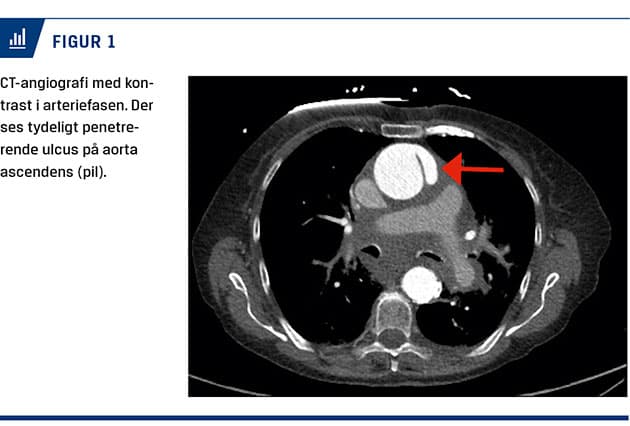

En CT-angiografi viste en ulceration i aorta ascendens (Figur 1) med indikation for thoraxkirurgisk intervention. Patienten blev vurderet som værende habil, fraset minutterne omkring det kliniske hjertestop. Hun ønskede ikke operation, trods information om højere mortalitetsrisiko ved konservativ behandling. Hun blev overflyttet til en thoraxintensiv afdeling til videre behandling i form af stram blodtrykskontrol, således at risikoen for yderligere perforering blev reduceret. Hun blev udskrevet i velbefindende på 12. dagen og var fortsat i live 36 måneder senere.